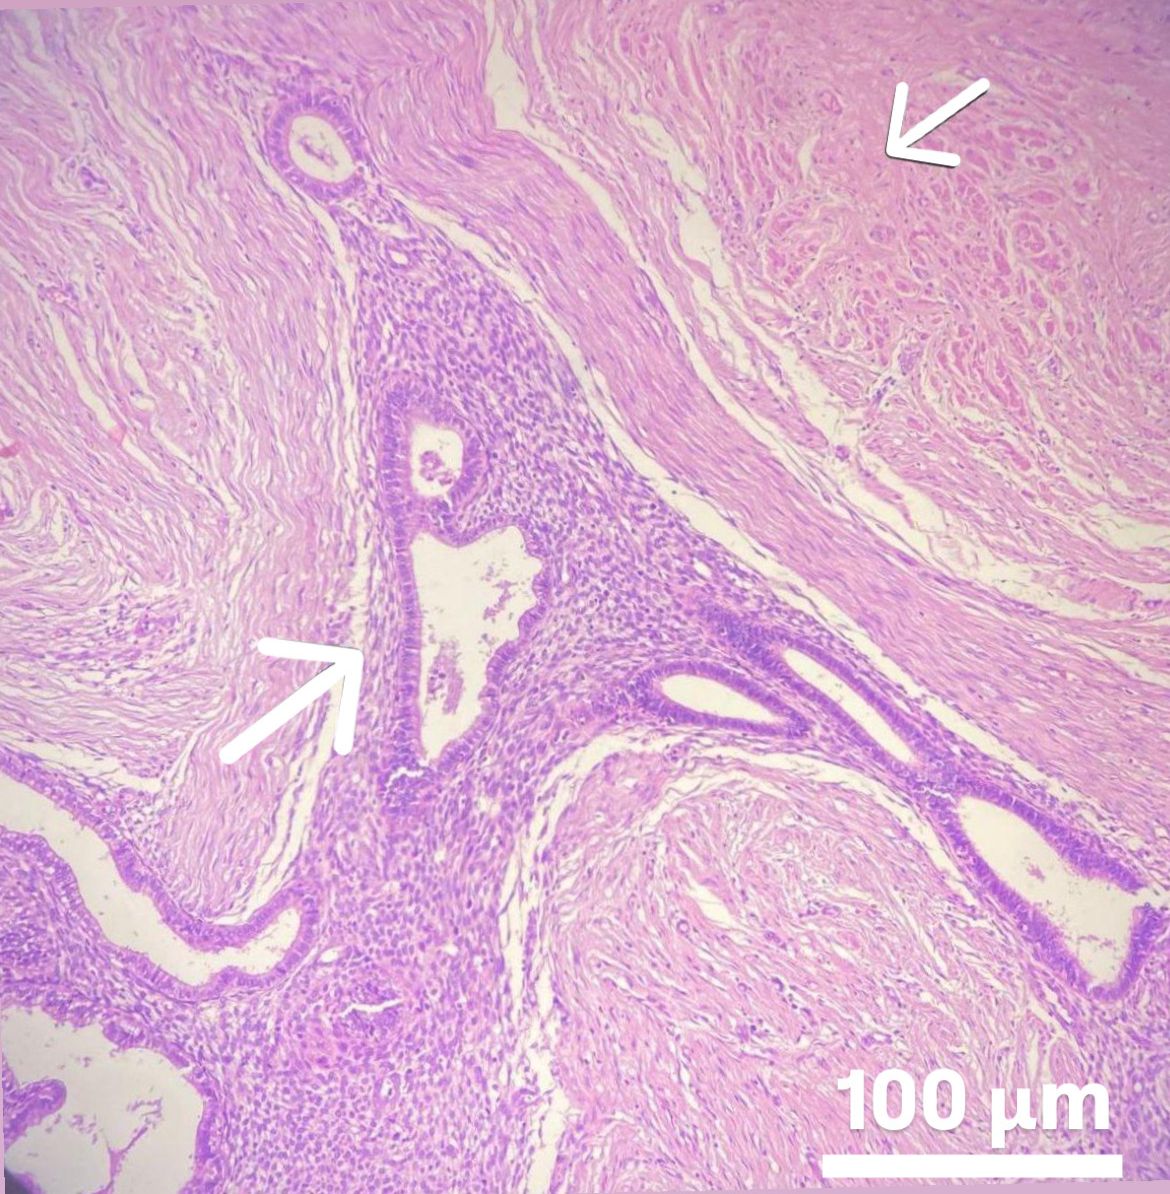

Abdominal wall endometrioma was detected in the physical and radiological examination (superficial ultrasound) (Fig. 4) of 204 patients who presented to our general surgery clinic due to complaints of swelling and pain in the abdominal wall. Masses were on the right side of the incision line in 160 (78.4%) patients. In the superficial ultrasound of the patients, AWE was above the rectus fascia in 110 patients and at the level of the rectus abdominis fascia in 94 patients. In only 1 patient, the mass was localized outside the cesarean scar site. Wide excision was performed under general anesthesia in 204 patients. The pathology of 203 patients was evaluated as compatible with endometrioma (Fig. 5). The pathology result of the remaining 1 patient was compatible with desmoid tumor. Postoperatively, only 1 patient had a hematoma. She recovered with conservative treatment. Repeat pregnancy was planned in 204 patients after an average of 2.5 years. AWE recurred in 9 of the patients in Group I during the follow-up period (4.4%). These patients underwent repeat total excision.

Fig. 5. Microscopic appearance of abdominal wall endometrioma. Arrows indicate ectopic endometrial tissue with preserved gland and stroma integrity within striated muscle and connective tissue. The rectus muscle is located in the upper right corner, while the abdominal wall endometrioma is visible in the lower left corner. Scale bar: 100 μm (H&E, hemtoxylin and eosin,